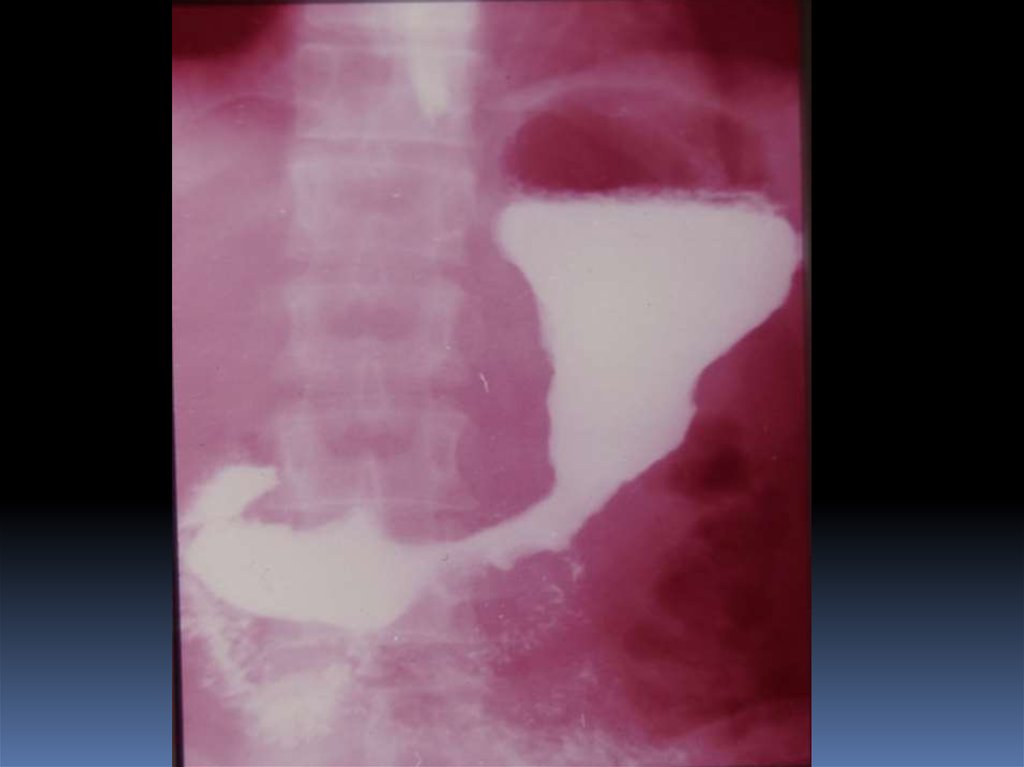

17. Классификация рака органов ЖКТ

1. Экзофитная форма:

2. Эндофитная форма:

узловая форма;

диффузноинфильтративная

форма;

полипоподобная

чашеподобная форма. инфильтративноязвенная.

3. СМЕШАННАЯ ФОРМА – 10-15%